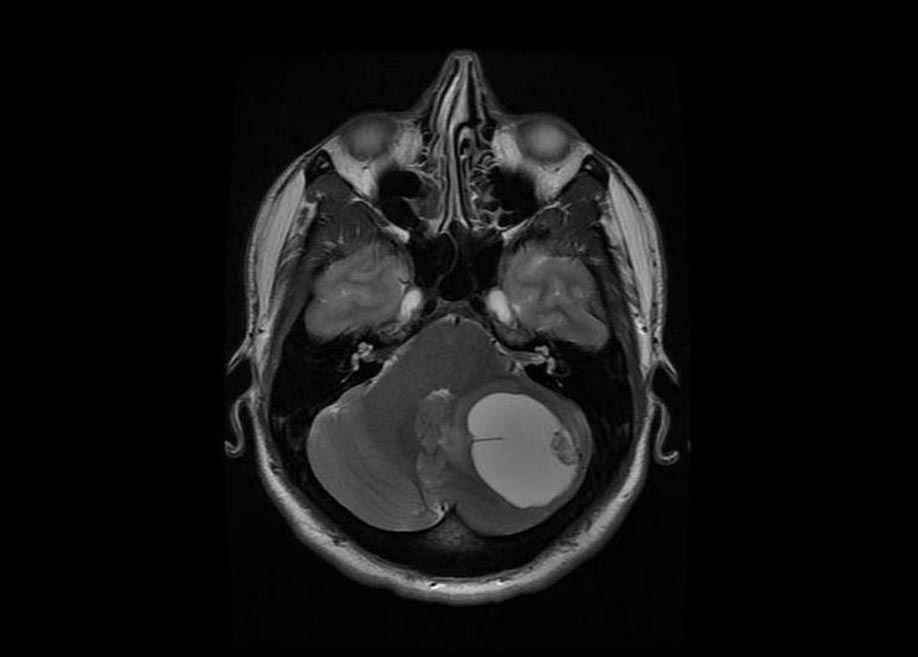

اصطلاح «تُنده‌ رگ تودِ مُخچه‌ ای» در فارسی، برابر با واژه‌ی علمی Cerebellar Hemangioblastoma در پزشکی است. این اصطلاح از سه بخش تشکیل شده است: «تنده‌ رگ» به معنای بافت یا توده‌ای است که دارای رگ‌های خونی فراوان و پرجریان است، «توده» به معنی رشد غیرطبیعی یا تومور در بافت بدن، و «مخچه‌ ای» به محل قرارگیری آن در مغز یعنی «مخچه» اشاره دارد. بنابراین، تنده رگ تود مخچه ای به توموری گفته می‌شود که در بخش مخچه‌ مغز ایجاد می‌شود و دارای بافتی پر از رگ‌های خونی است. این نوع تومور معمولاً خوش‌خیم (غیرسرطانی) است و رشد آن آهسته صورت می‌گیرد، اما به دلیل فشار بر بافت‌های اطراف مغز، می‌تواند علائمی مانند سردرد، سرگیجه، اختلال در تعادل و تهوع ایجاد کند. از نظر پاتولوژیک، این توده از سلول‌های اندوتلیال (پوشاننده‌ی رگ‌ها) و سلول‌های استرومایی تشکیل شده است. در برخی موارد، این بیماری با سندرمی ژنتیکی به نام فون هیپل–لینداو (Von Hippel–Lindau) همراه است. تشخیص آن معمولاً با روش‌های تصویربرداری مانند MRI انجام می‌شود. درمان اصلی، جراحی برای برداشتن کامل توده است.

{cerebellar hemangioblastoma} [علوم پایۀ پزشکی] تنده رگ تودی اغلب کیسه ای که در مخچه ایجاد می شود